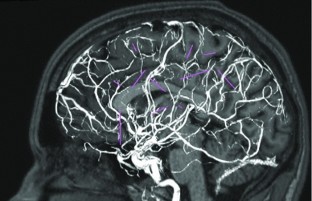

StereoElectroEncephaloGraphy (SEEG) is done to identify the epileptogenic zone of the brain using several multi-lead electrodes whose positions in the brain are pre-operatively defined. Intracranial hemorrhages due to disruption of blood vessels can cause major complications of this procedure (\(<\)1 %). In order to increase the intervention safety, we developed and tested planning tools to assist neurosurgeons in choosing the best trajectory configuration.

An automated planning method was developed that maximizes the distance of the electrode from the vessels and avoids the sulci as entry points. The angle of the guiding screws is optimized to reduce positioning error. The planner was quantitatively and qualitatively compared with manually computed trajectories on 26 electrodes planned for three patients undergoing SEEG by four neurosurgeons. Quantitative comparison was performed computing for each trajectory using (a) the Euclidean distance from the closest vessel and (b) the incidence angle.

Quantitative evaluation shows that automatic planned trajectories are safer in terms of distance from the closest vessel with respect to manually planned trajectories. Qualitative evaluation performed by four neurosurgeons showed that the automatically computed trajectories would have been preferred to manually computed ones in 30 % of the cases and were judged good or acceptable in about 86 % of the cases. A significant reduction in time required for planning was observed with the automated system (approximately 1/10).